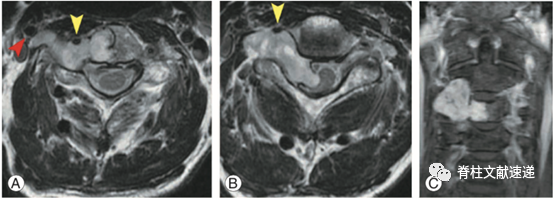

1.4.2 硬膜内+硬膜外+椎间孔+椎体+椎旁(黄箭头:椎动脉,红箭头:颈动脉)